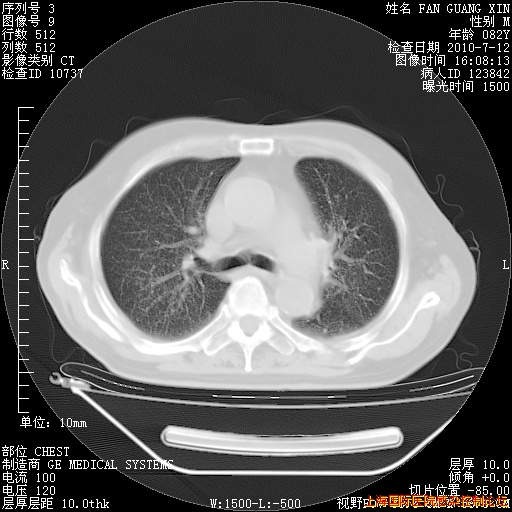

今天复查CT

今天CT

整整相隔30天的肺部CT好像有所好转啊。甲强龙减量第3天,需要观察体温。